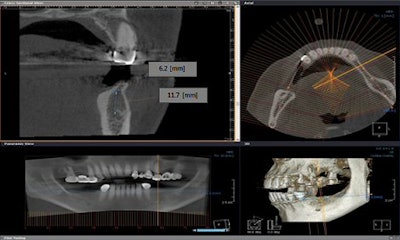

Image clarity: What 3D images gain in perspective, they often sacrifice in clarity. 3D images tend to be grainy and have a granular quality. Look for models with the smallest voxel sizes: As voxel sizes decrease, the clarity of the image increases correspondingly.

Field-of-view: This refers to the size of the image displayed by the scanner. Having a range of options is more important than the biggest possible field-of-view. The larger an area you scan, the higher the radiation dosage to which you expose the patient. A larger field-of-view can mean less clarity as well, says Steve White of J. Morita of Irvine, Calif. "If a clinician is only doing one or two implants," says Dr. Ganz, "he or she may not need a large machine that has a large field-of-view."